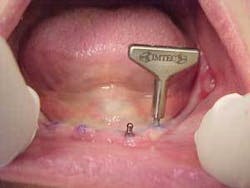

Mini-implants, which were first developed by Dr. Victor I. Sendax of New York in the early 1970s and later marketed by IMTEC Corporation in the 1990s, are just now beginning to realize their potential. Much of this is due to the sudden realization that these tools can have extreme benefits to patients. Due to their small size, mini-implants are logically less expensive than conventional implants. This lower initial cost is passed along to the patient through an overall more cost-effective procedure. This, though, may be the least among the list of benefits that has spurred the growth of mini-implants. With the Sendax IMTEC MDI (mini dental implant) surgical protocol, there are numerous physical benefits to the patient, which in the end are benefits to the clinician.

Clinicians working with MDIs have quickly learned that there is no waiting for the osseointegration process. Dentists have noted from positive patient feedback that MDIs cause much less discomfort than conventional implants, and patients are pleased with such a quick procedure. With thousands of MDIs in place, doctors have learned that the procedure is ideal for medically compromised, aging, and financially compromised patients. By introducing this tool into his Tustin, Calif., practice about seven years ago, co-author Dr. Choi has been able to assist numerous patients who were not good candidates for conventional implants or who could not afford conventional implant therapy.